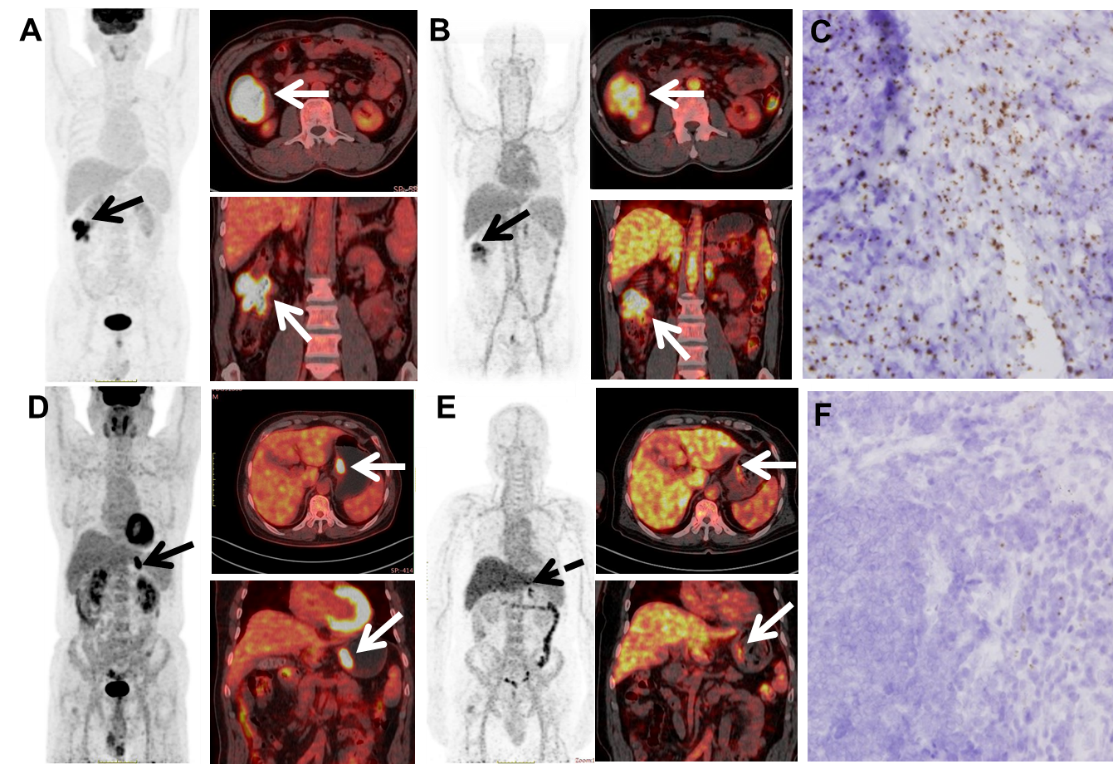

图. 两名患者的18F-FDG PET/CT(A.D)、89Zr-CTB006 PET/CT(B.E)图像及RNAscope(C.F)图像

研究表明,在开展 DR5靶向治疗之前,对肿瘤DR5表达量的测定至关重要。特异性 PET/CT分子探针可用于检测肿瘤组织中DR5表达水平,有望用于DR5治疗潜在获益患者的筛选,为DR5单抗的临床应用提供一个至关重要的助力。此外,DR5靶向PET探针的开发及临床转化,可进一步阐明DR5受体在胃肠肿瘤的在体表达、代谢与分布情况,有助于后续靶向药物的开发。